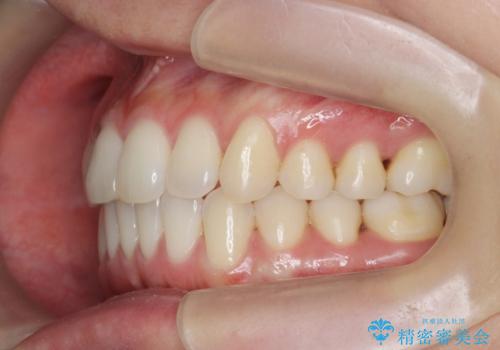

前歯のねじれを改善 マウスピース矯正インビザライン

- 目立つ前歯のねじれを改善したい、と矯正治療を希望され来院されました。

左側の奥歯は後方移動を行うことで、理想的な噛み合わせに整えるとともに、前歯の突出感も同時に改善することができました。